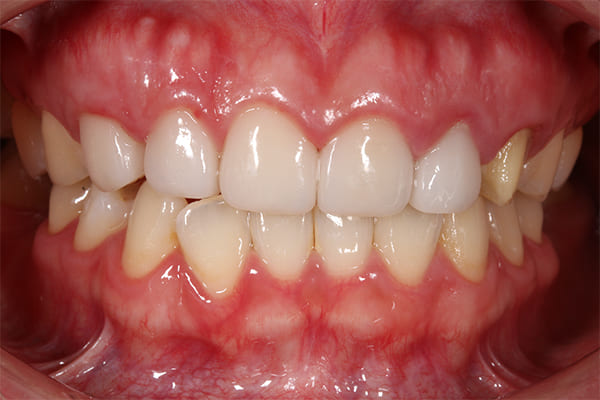

こちらは、歯周外科手術の前と後の比較写真です。

術前と比べて、歯ぐきの位置が整い、歯が自然に長く見えるようになっているのがわかります。

これは歯ぐきのバランスを整えることで、歯の見え方をより美しく改善した結果です。

こちらが最終補綴物を装着した後の口腔内写真です。

初診時に見られた歯肉の炎症は改善し、健康的で引き締まった歯肉へと回復しています。

補綴物も高い透明感と自然な質感を備えており、審美性・機能性ともに理想的な仕上がりとなりました。